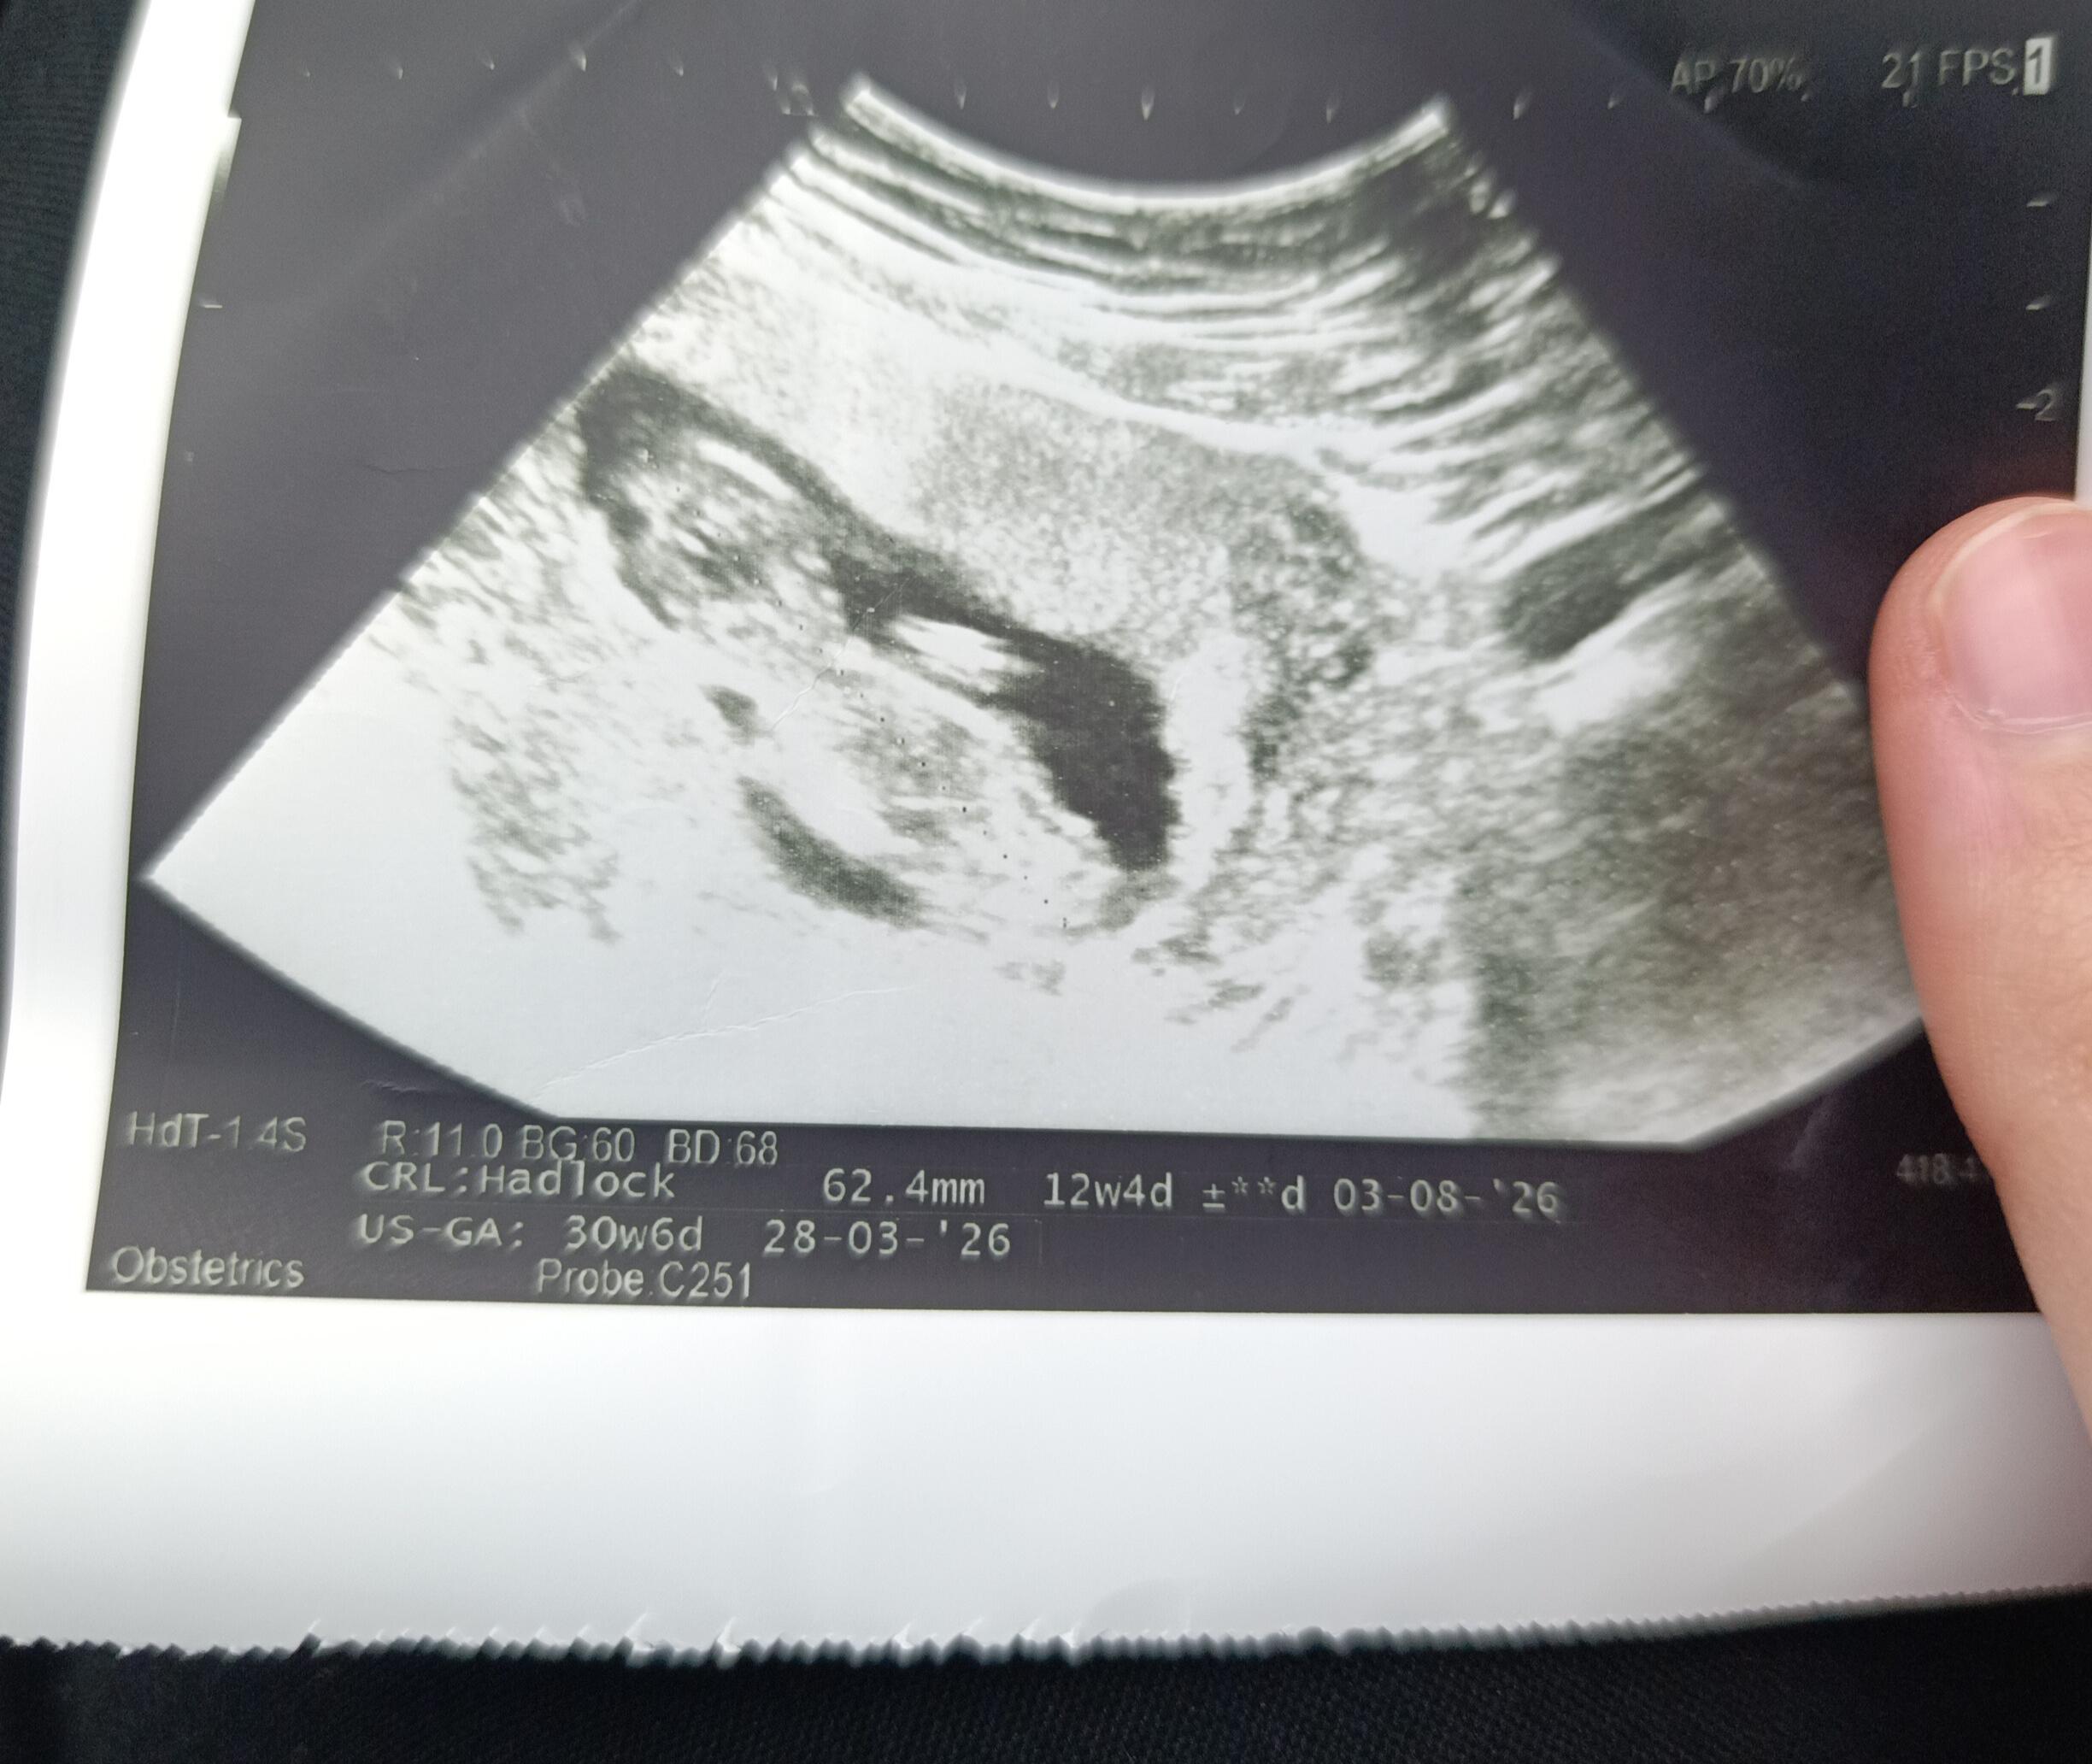

Kız dedi doktorum ![]()

Baska foto varmi tam net gozukmuyor kese

Kız hissettim Allah tamamına erdirsın insallah

Evet kiza benziyo bence de![]()